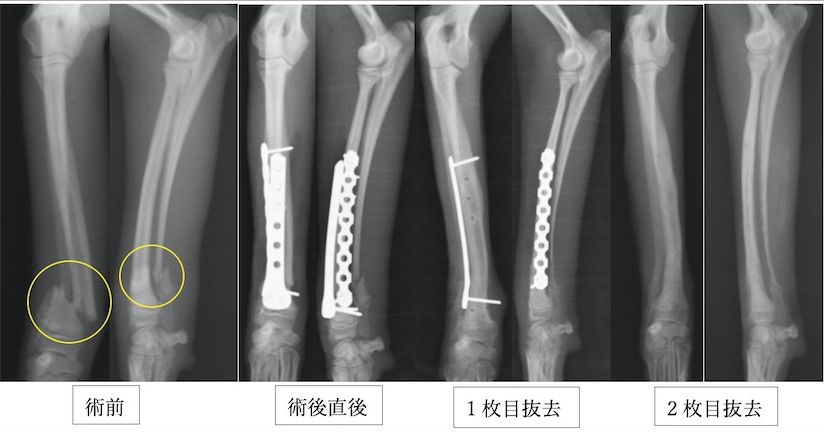

近年、小型犬が増加しているのに比例して橈尺骨骨折が増加しています。橈尺骨骨折にはプレートを2枚入れる方法を用います。2枚入れることで強度を増すことができプレートの破綻を防止できます。また、1枚ずつプレート抜去が可能であるため、ある程度骨が固まってきたら1枚抜去し、さらに骨化を促進し、もう一枚抜去するという方法が可能です。そうすることで癒合不全(骨化が遅れること)を防止し、プレート抜去後の再骨折のリスクを減らすことができます。

イタリアングレーハウンドの橈尺骨骨折です。2.0mmスクリューを使用しています。